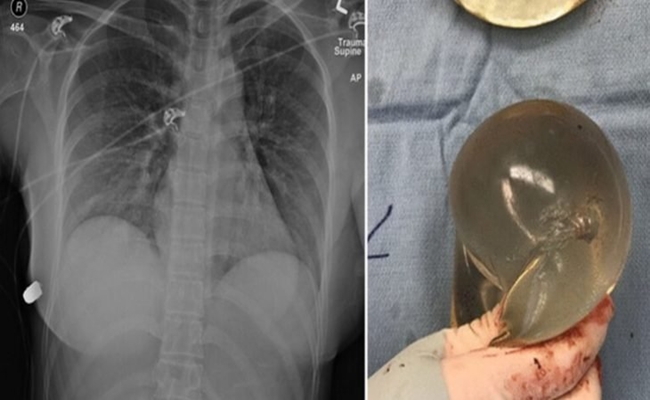

وكشفت دراسة نشرت الأسبوع الماضي في مجلة “سايج” الطبية تناولت حالة هذه المرأة أن حشوة السيليكون في الثدي الأيسر للشابة البالغة من العمر 30 عاما، ساهمت في انحراف الرصاصة بعيدا عن أعضائها الحيوية إلى الثدي الآخر.

ثم أزالوا حشوة السيليكون وصوروها بهدف دراستها وقد أظهرت الأشعة المقطعية أن الرصاصة مرت عبر الحشوة اليسرى وضربت اليمنى.

وقال معدو الدراسة: “بناء على مسار دخول الرصاصة إكلينيكيا وتقويمها إشعاعيا، فإن المصدر الوحيد لانحراف الرصاصة هو حشوة الثدي الأيسر”.